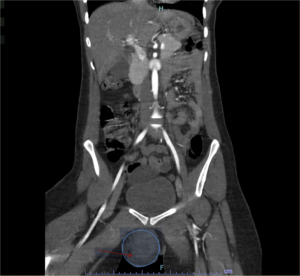

Vulvar Hematoma. CT Coronal, Annotated. JETem 2024

Vulvar Hematoma. CT Coronal Annotated. JETem 2024